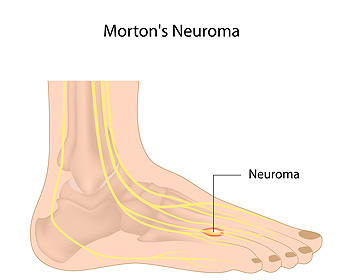

Just about anyone can develop Morton’s Neuroma, a foot ailment that can be particularly painful and troublesome. However, some individuals may be at an increased risk of developing this condition, so it is important to discern your own level of risk. Morton’s neuroma primarily affects plantar digital nerves that run between the metatarsal bones of the foot. In most cases, Morton’s neuroma targets the nerve between the third and fourth metatarsal bones, resulting in pain. Although the exact cause of Morton’s neuroma is somewhat elusive and largely case-dependent, it is most likely caused by either extended straining and compression of the plantar digital nerves or inflamed joints surrounding these nerves. Certain individuals can be more susceptible to Morton’s neuroma than others. For example, approximately 75% of those who suffer from this condition are women. This is most likely due to the fact that women wear shoes such as high heels that compress the toes, putting the plantar digital nerves at risk. Additionally, ballet dancers who wear similarly restrictive footwear are at an increased risk of developing Morton’s neuroma. Individuals between the ages of 40 and 50 are typically at the highest risk of developing this condition. If you believe you may have Morton’s neuroma or are in one of these high risk categories, you might consider contacting a podiatrist.

Morton’s Neuroma

Morton's neuroma is a painful foot condition that commonly affects the areas between the second and third or third and fourth toe, although other areas of the foot are also susceptible. Morton’s neuroma is caused by an inflamed nerve in the foot that is being squeezed and aggravated by surrounding bones.

What Increases the Chances of Having Morton’s Neuroma?

- Ill-fitting high heels or shoes that add pressure to the toe or foot

- Jogging, running or any sport that involves constant impact to the foot

- Flat feet, bunions, and any other foot deformities

Morton’s neuroma is a very treatable condition. Orthotics and shoe inserts can often be used to alleviate the pain on the forefront of the feet. In more severe cases, corticosteroids can also be prescribed. In order to figure out the best treatment for your neuroma, it’s recommended to seek the care of a podiatrist who can diagnose your condition and provide different treatment options.